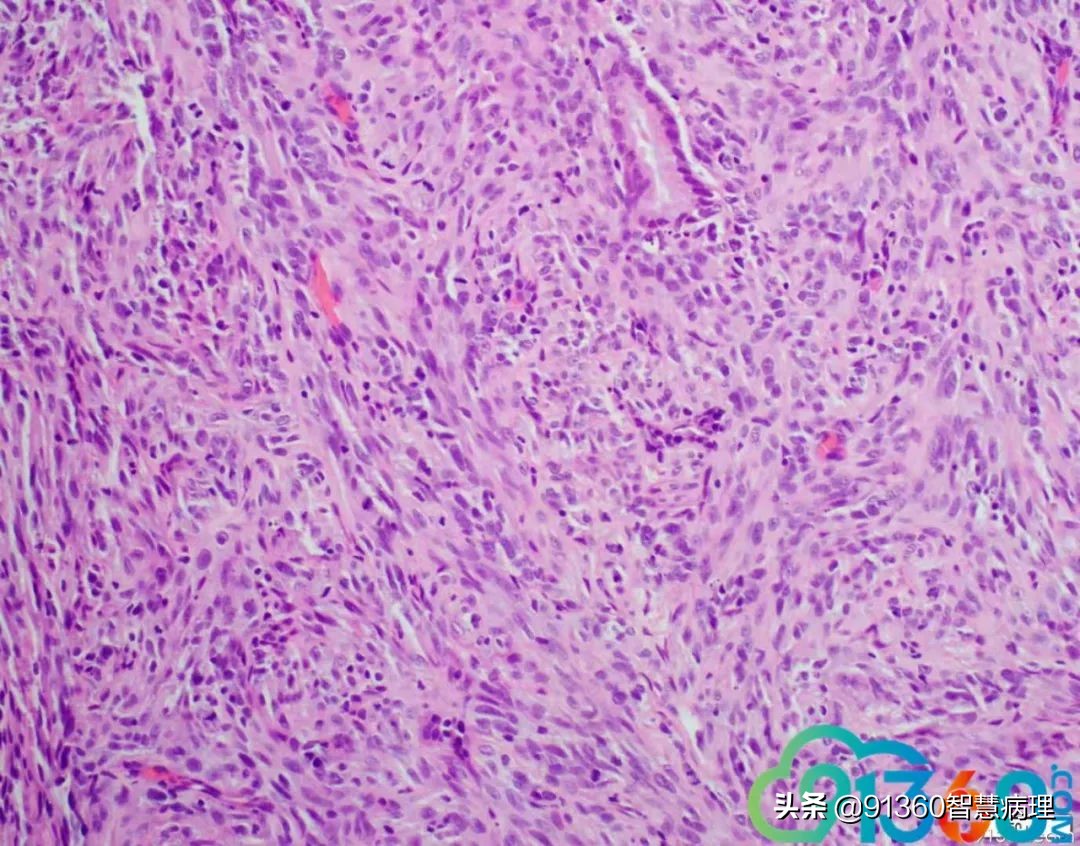

邢德印 Desmin -Sarcomatoid carcinoma; spindle cell carcinoma 石岩 @邢德印(妇科病理) 好例子 邢德印 以前没见过这么明显的,太肉瘤样了 任永昌 @邢德印(妇科病理) 赞 郭晓静 @邢德印(妇科病理) 我偏向猜的答案也是这个,。谢谢分享! 王昀 @邢德印(妇科病理) 好例子,没见过这么弥漫肉瘤样的,回过头来看,好像还是有点结构的样子

邢德印 @王昀 301 圈里的是mitosis 任永昌 @邢德印(妇科病理) @王昀 301 实际上,上边这个腺体有异型,核过于大。

王昀 哦,我说那个裂隙,有点像腺的结构 邢德印 @临沂市中心医院任永昌 @王昀 301 腺体其实是entrapped,正常的腺体 王昀 我是想起乳腺的化生性癌,所以想看看有没有腺和梭形细胞过渡移行的地方,能找点线索,可能是知道答案后开始想象了,这个可能是假腺